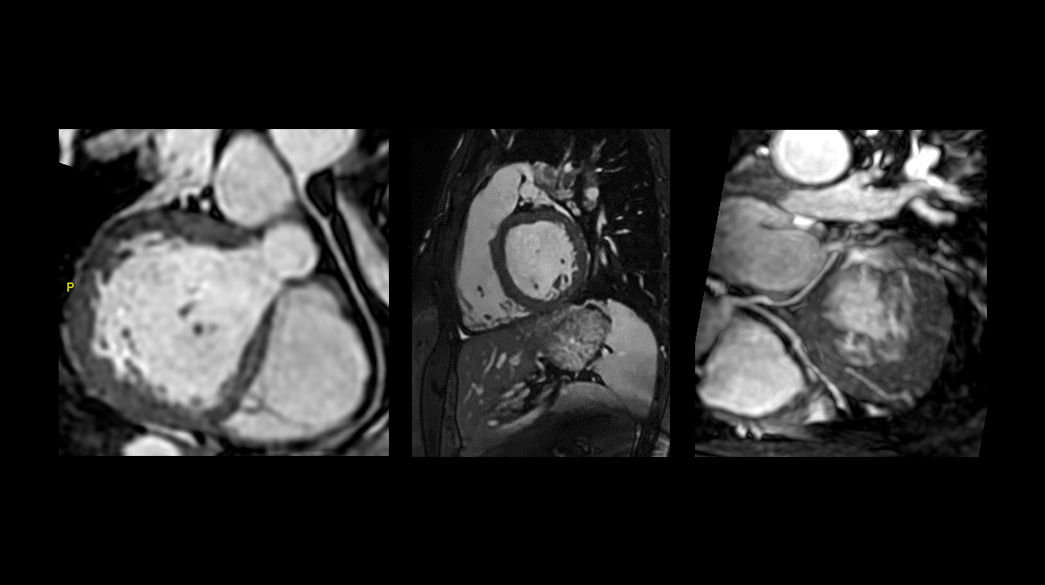

MDE Plus – compatible with AIR™ Recon DL

Inversion-based cardiac gated acquisition that enhances the contrast between infarcted and normal myocardium, accommodates difficult-to-scan patients

MDE FatSat – compatible with AIR™ Recon DL

Volumetric approach to assess myocardial enhancements and atrial wall enhancements. Compatible with navigator for free breathing scans

SSH (PS) MDE with Respiratory Triggering – compatible with AIR™ Recon DL

Allows for a total free breathing and real time acquisition of late gadolinium Enhancement. Also available with Phase Sensitive technique